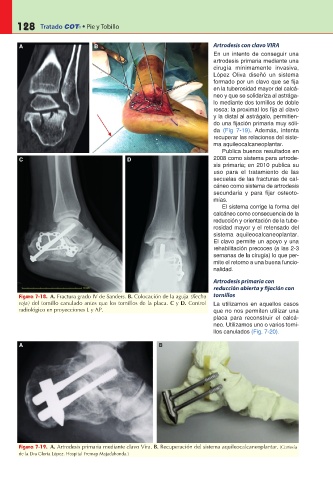

A B Artrodesis con clavo VIRA

En un intento de conseguir una

artrodesis primaria mediante una

cirugía mínimamente invasiva,

López Oliva diseñó un sistema

formado por un clavo que se fija

en la tuberosidad mayor del calcá-

neo y que se solidariza al astrága-

lo mediante dos tornillos de doble

rosca: la proximal los fija al clavo

y la distal al astrágalo, permitien-

do una fijación primaria muy sóli-

da (Fig 7-19). Además, intenta

recuperar las relaciones del siste-

ma aquileocalcaneoplantar.

Publica buenos resultados en

C D 2008 como sistema para artrode-

sis primaria; en 2010 publica su

uso para el tratamiento de las

secuelas de las fracturas de cal-

cáneo como sistema de artrodesis

secundaria y para fijar osteoto-

mías.

El sistema corrige la forma del

calcáneo como consecuencia de la

reducción y orientación de la tube-

rosidad mayor y el retensado del

sistema aquileocalcaneoplantar.

El clavo permite un apoyo y una

rehabilitación precoces (a las 2-3

semanas de la cirugía) lo que per-

mite el retorno a una buena funcio-

nalidad.

Figura 7-19. A. Artrodesis primaria mediante clavo Vira. B. Recuperación del sistema aquileocalcaneoplantar. (Cortesía

de la Dra Gloria López. Hospital Fremap Majadahonda.)